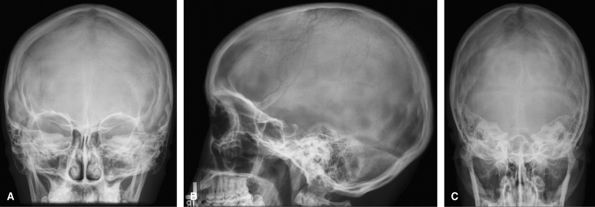

Vertebral Column

Not used very often because most indications for a skull

radiograph are better served by a CT. Can still be used to assess shunt

continuity.

![]() |

Figure 44 (A) PA skull. (B) Lateral skull. (C) Townes view.